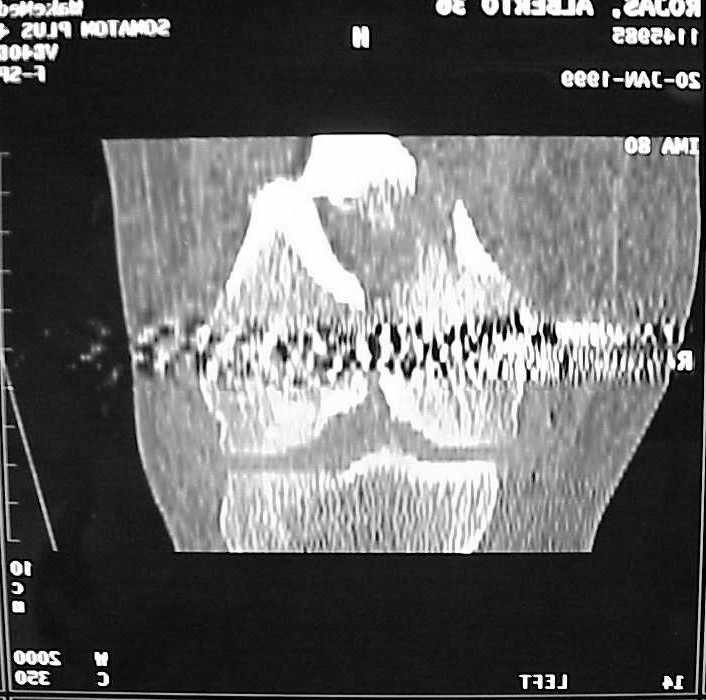

A CT and knee xrays would help identify lateral condyle comminution and/or a "hoffa fragment" of the posterior condyle. I am concerned that the lateral cortex is not sufficient to give purchase for a retrograde IMN. blocking screws could improve this as a possibility. A long blade or LISS if avaible would be my secondary choices. Good luck. Any chance you can get these cases transferred earlier when it

See attached case that was done several years ago before LISS. He had comminuted trochlea and anterior blocking screws were used to prevent anterior IMN cut-out.